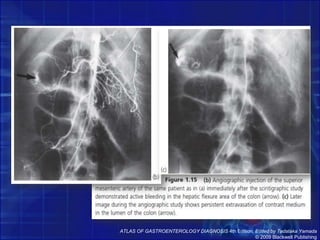

ATLAS OF GASTROENTEROLOGY DIAGNOSIS 4th Edition, Edited by Tadataka Yamada© 2009 Blackwell Publishing